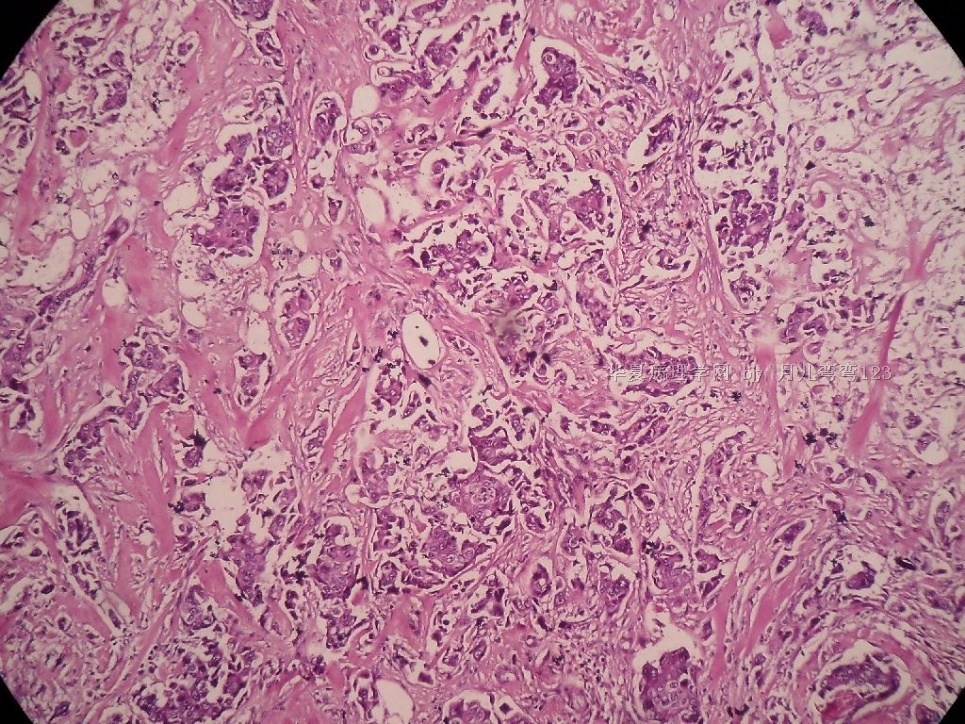

姓    名: ××× 性别:  女 年龄:  45

标本名称:  左侧近乳晕处肿物

简要病史:  患者描述有疼痛

肉眼检查:  肿物一个2.5*2*1厘米,切面灰白质地硬。

• 浸润性导管癌?图1

上皮样细胞,大部分粘附成团成巢,明显浸润。大部分细胞大,核级别高,少数图中见松散的小细胞。未见原位癌。

大细胞考虑浸润性导管癌(3级),小细胞要排除小叶癌。如果有条件请做免疫组化。

Most likely it is INVASIVE DUCTAL CARCINOMA.

DO ER/PR/HER2 STAINS

应该是浸润性导管癌,标本可能有部分自溶现象。